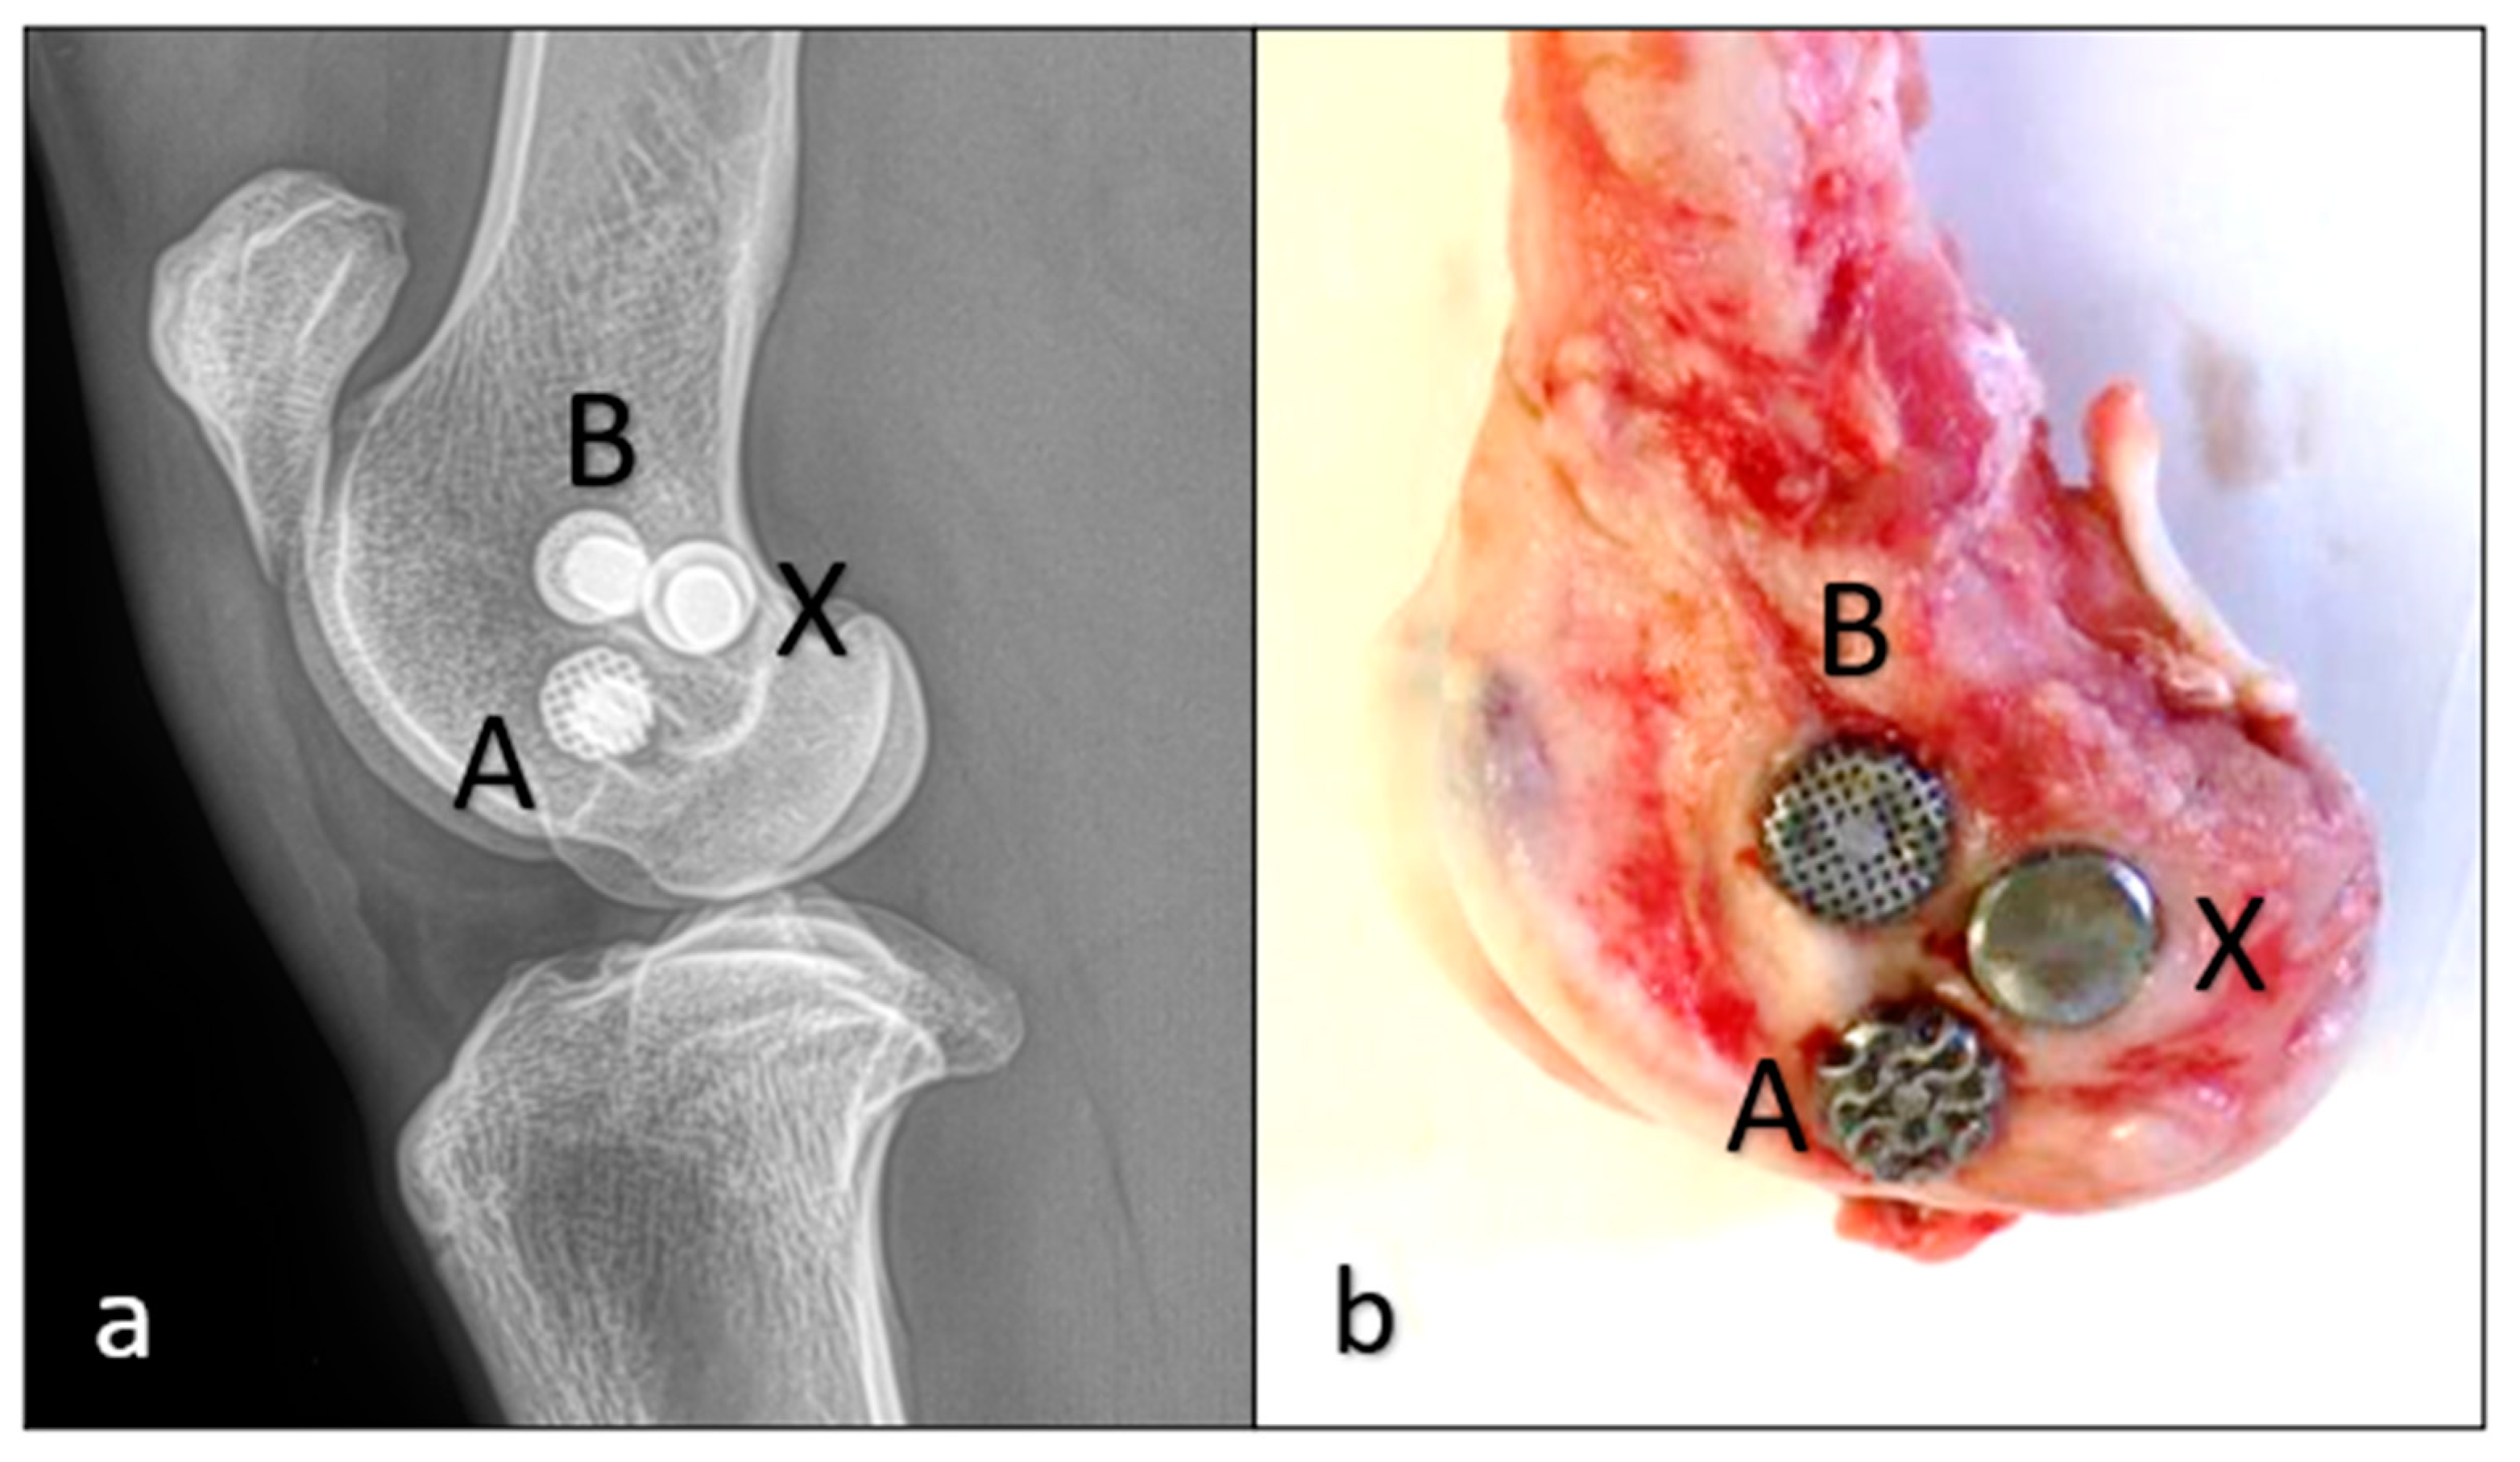

| Sheep | Grid Shape of Implanted Implants | Time of Euthanasia |

|---|---|---|

| 1. | “A” gyroid, “B” cube, “X” solid | 8 weeks |

| 2. | “A” gyroid, “B” cube, “X” solid | 8 weeks |

| 3. | “A” gyroid, “B” cube, “X” solid | 12 weeks |

| 4. | “A” gyroid, “B” cube, “X” solid | 12 weeks |